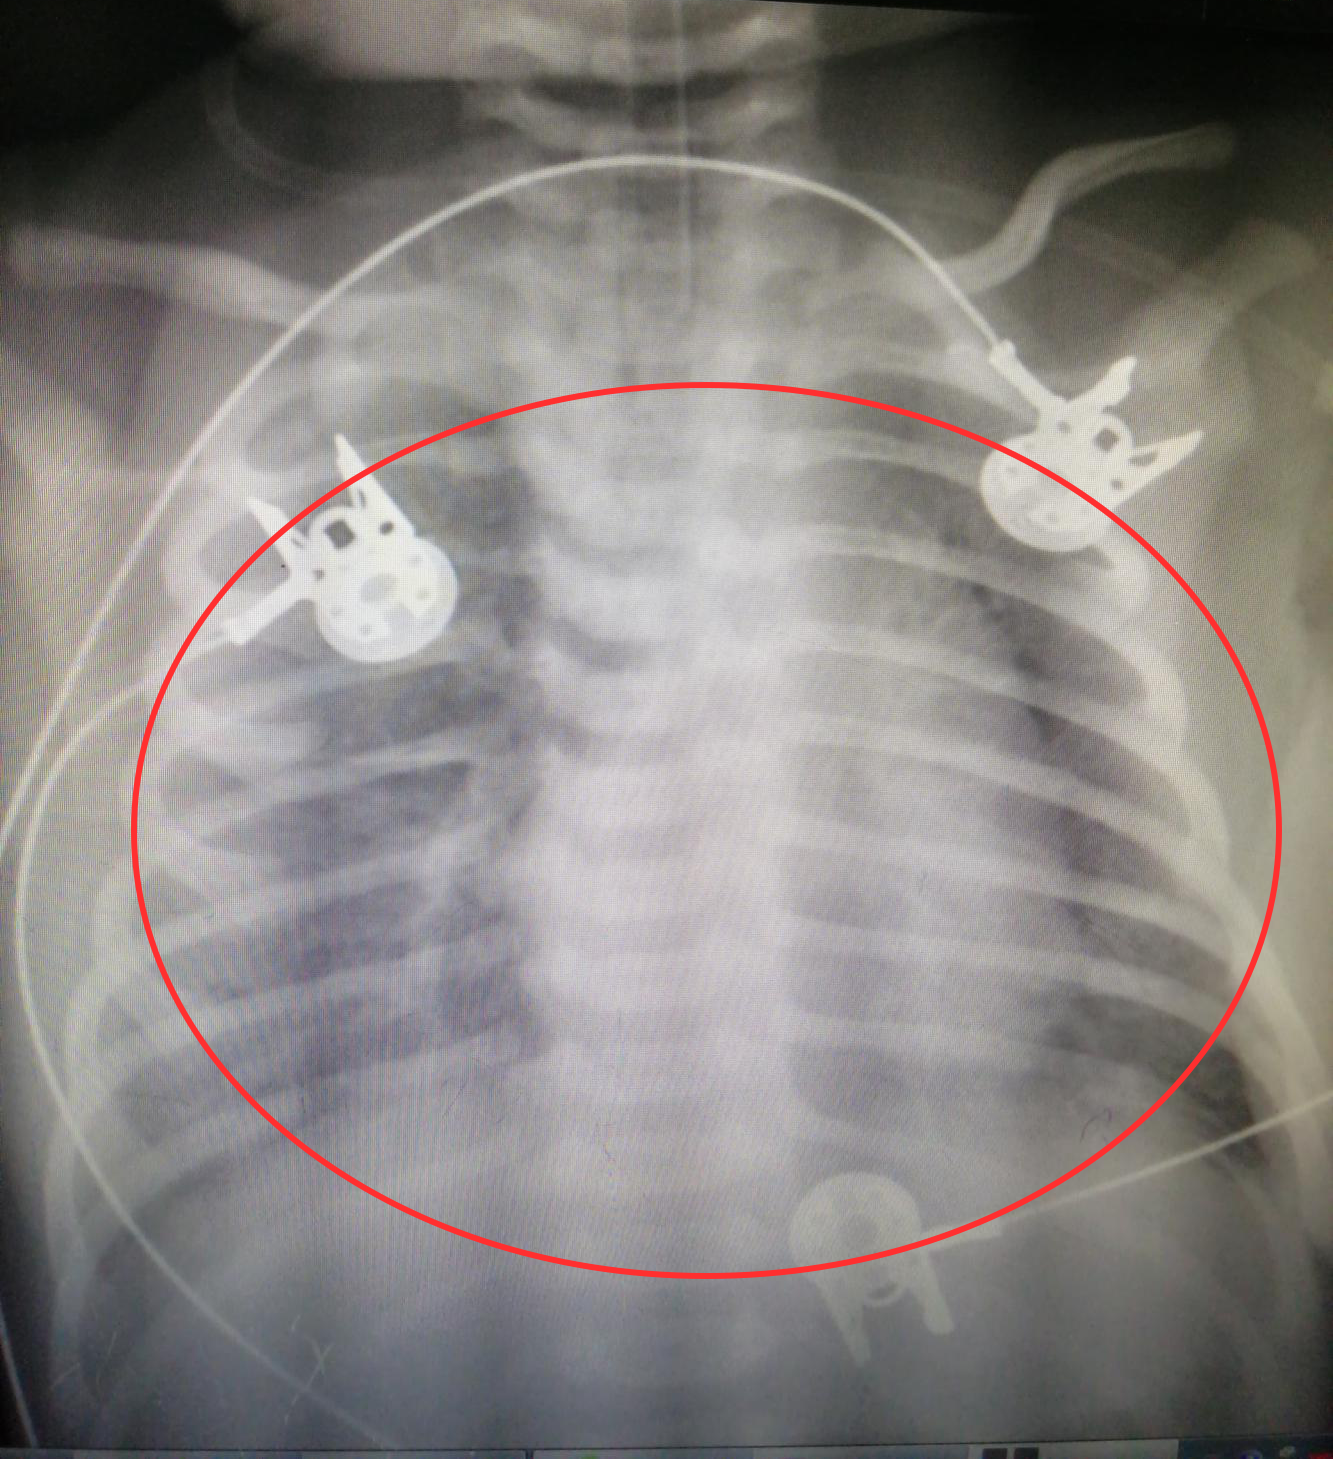

患儿入院时肺出血X线片 ,双肺和心脏、双肺和膈肌界线模糊不清